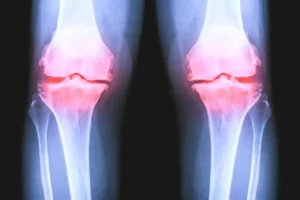

Gonartrosi femoro tibiale

Il ginocchio è una struttura complessa e fondamentale del nostro corpo. Collega la coscia e la gamba, permettendoci di muoverci liberamente. La cartilagine articolare svolge un ruolo primario in quest’area, proteggendo e ammortizzando le ossa degli arti inferiori durante i movimenti. La struttura anatomica del ginocchio Il ginocchio si compone di due articolazioni principali: la prima … Continued